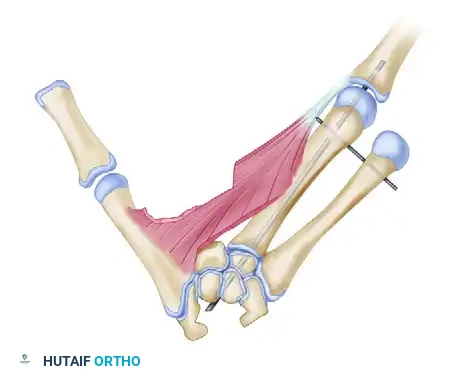

3. Index Ray Transposition and Osteotomy

With the soft tissues released, the structural reconstruction begins.

- Perform a transverse or slightly oblique osteotomy at the base of the index metacarpal.

- Mobilize the entire index ray and transfer it ulnarly to align with the base of the third metacarpal.

The index finger is transposed following the osteotomy of the index metacarpal base and the release of the first dorsal interosseous muscle.

- Bone Fixation: If the third metacarpal base is hypoplastic or small, shape the proximal end of the transposed index metacarpal into a peg and impale it directly into the medullary canal of the third metacarpal base.

- If adequate bone stock is present, reduce the osteotomy and fix the index metacarpal to the third metacarpal base using crossed or parallel Kirschner wires (K-wires).

Additional subperiosteal release of the first dorsal interosseous allows tension-free transposition. The inset demonstrates the necessary rotation (up to 45 degrees) required to prevent digital overlap during flexion.

Clinical Pearl: Rotational alignment is the most critical aspect of the osteotomy. The transposed digit must be supinated (often up to 45 degrees) to ensure it flexes symmetrically into the palm without scissoring over the ring finger.